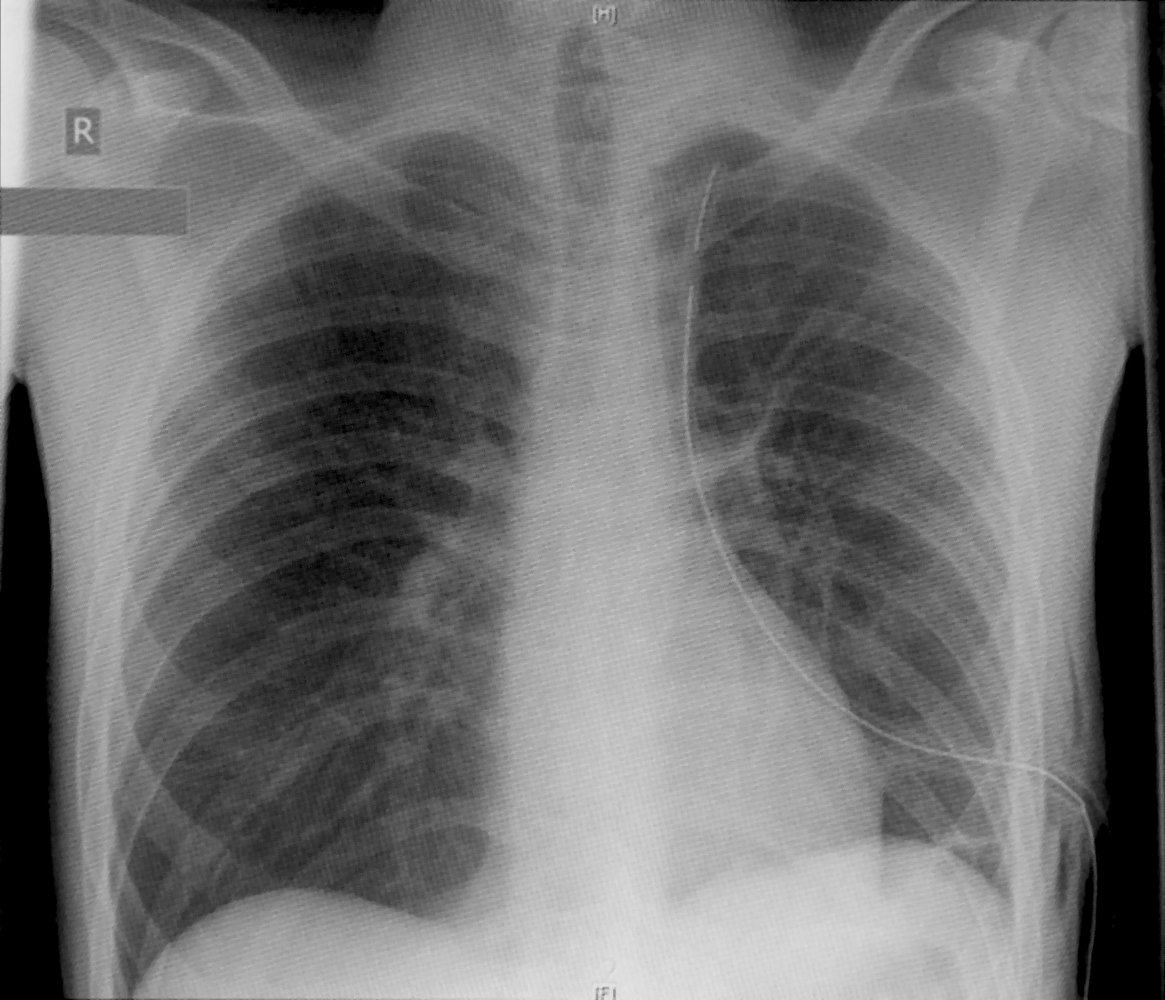

- Confirm tube placement and patency clinically and on CXR.

Chest tube placement confirmed on CXR

- All gaps in radiopaque line within pleural cavity

- No kinks along the length of the tube